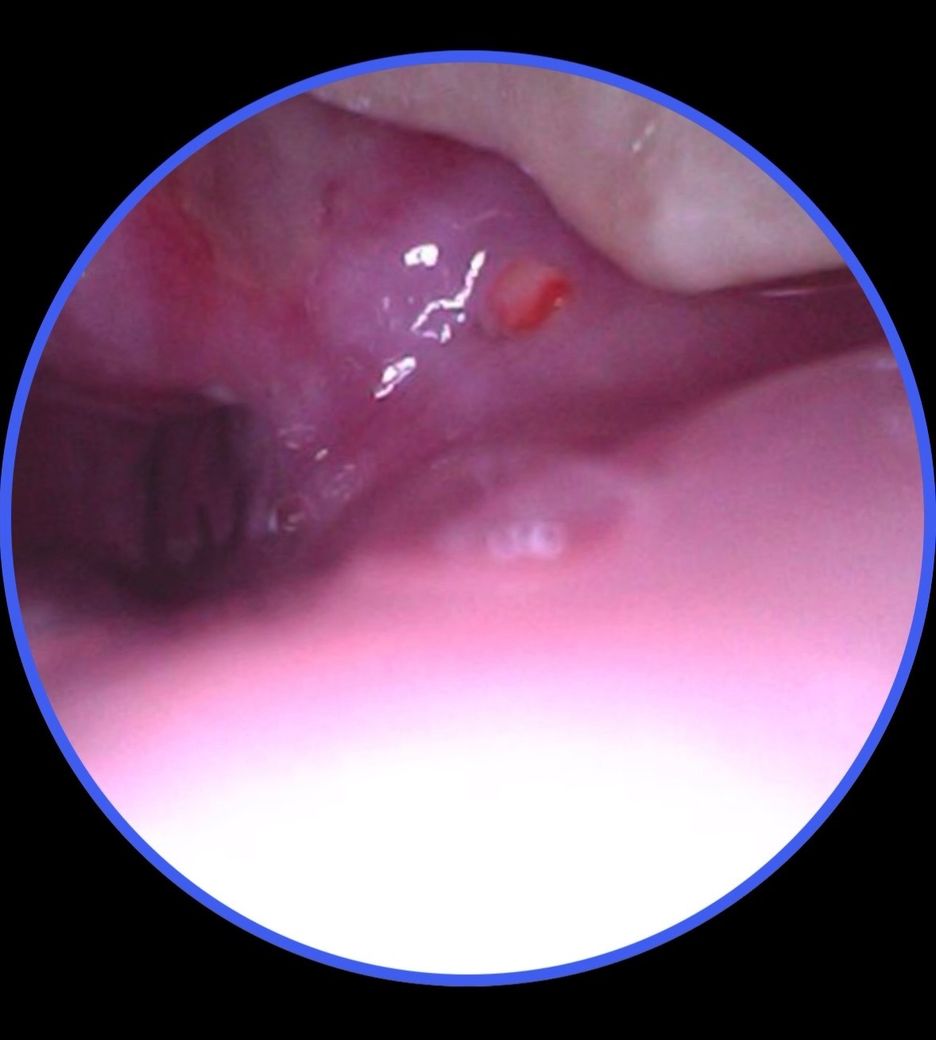

윗 사랑니 뒤쪽에 빨간게 나고 주변이 하얗게 됐습니다.

통증이 있고 특히 뭐 먹을 때나 입을 크게 벌리면 눌리면서 많이 아픕니다. 구내염은 보통 하얀색인데 이건 보니까 빨갛게 올라왔고 주변이 하얗게 됐습니다.

• 2번 째 사진

해당부위는 사랑니가 맹출이 되는 과정으로 보입니다.

잇몸 주변에 염증이 보이고 있으며 사랑니로 인해서 염증이 생겼다면 사랑니를 발치 하는것이 좋습니다.

사랑니 위생관리 부족 등의 문제로 주변 잇몸부에 염증이 유발된 것 같습니다. 발치 상담 받아보세요